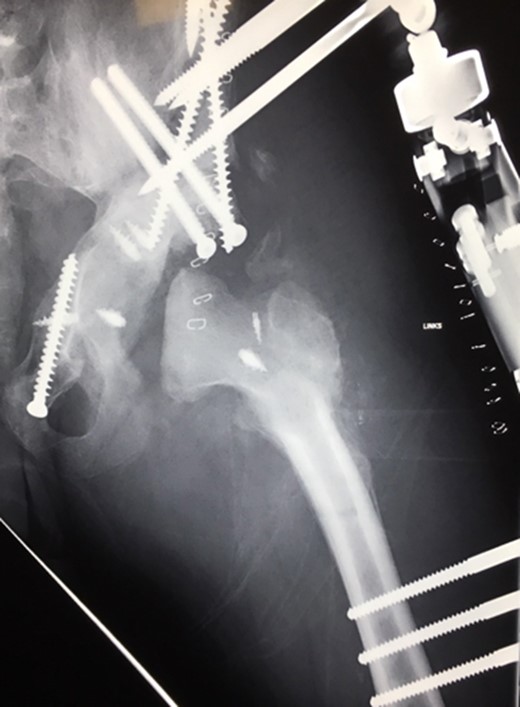

(2008) Despite reconstruction the femoral head subluxated and rapidly lost congruency. An open reduction and capsular reconstruction with trevira tube, removal of the femoral plate and temporary fixation with an external fixator with movable hip mechanism for flexion of the joint (Orthofix MonoRail) was performed.